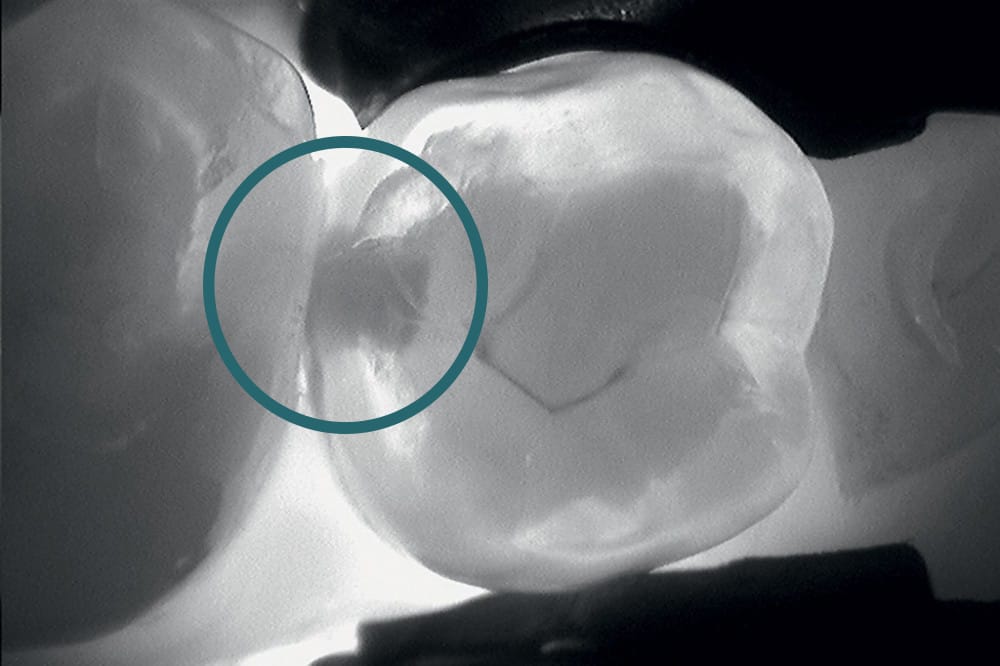

La DIAGNOCam KAVO Vision Full HD est un outil de diagnostic dentaire non invasif et sans rayons X.

Il permet de détecter les caries occlusales et proximales ainsi que les fissûres, de manière totalement indolore.

Cette caméra utilise la transillumination* (par fibre optique) ainsi que la fluorescence pour un diagnostic complet.

*La transillumination consiste à projeter une lumière intense (infrarouge) à travers les tissus pour visualiser par transparence les lésions.

Celles-ci apparaissent en sombre car la structure dentaire saine, laisse passer la lumière contrairement aux tissus carieux.